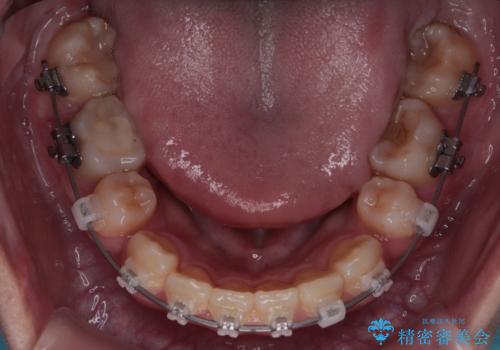

結果的に1年半で、再度転勤になる前に治療を終えることができました。

- 1年6ヶ月